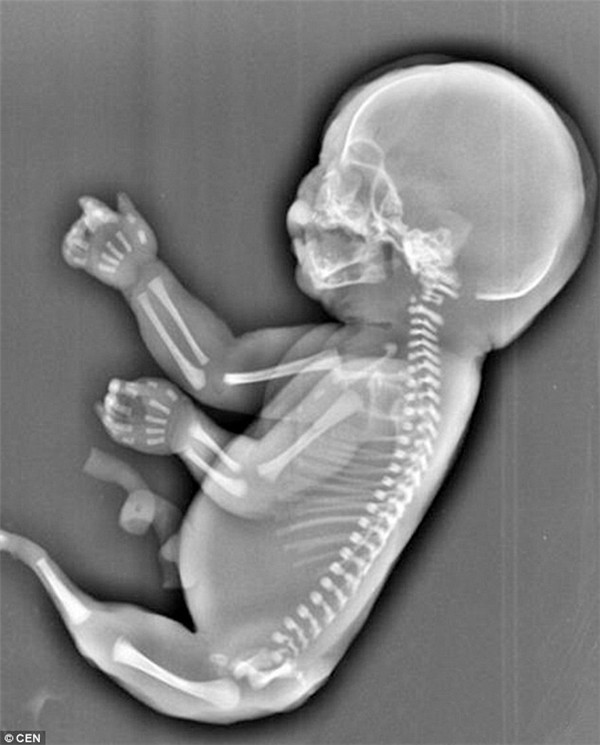

Hội chứng nàng tiên cá hay còn gọi là hội chứng người cá (hội chứng Mermaid) là một rối loạn phát triển bẩm sinh cực kỳ hiếm gặp.

Trẻ sơ sinh bị ảnh hưởng sinh ra với hai chân hợp lại một phần hoặc toàn bộ. Các dị tật khác kèm theo cũng có thể xảy ra bao gồm các bất thường ở đường sinh dục tiết niệu, các bất thường ở đường tiêu hóa, dị tật cột sống thắt lưng, xương chậu và không có hoặc kém phát triển của một hoặc cả hai thận.

| Hội chứng Mermaid là một căn bệnh quái ác từ khi còn nằm trong bào thai. Ảnh minh họa |